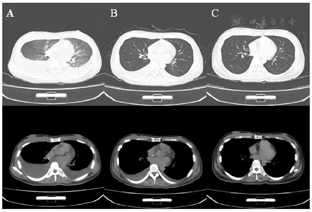

患者骨髓涂片、免疫分型、染色体、BCR-ABL基因定量和ABL突变结果明确诊断为慢性髓系白血病急淋变,ABL F317L、Y253H突变。头颅CT显示头颅硬膜下血肿,大脑镰疝,胸部CT示肺部感染,胸腔积液。

3.影像学结果:(1)头颅CT结果(图2)。(2)胸部CT结果(图3)。(3)心电图和心超未见明显异常。

患者治疗后症状明显缓解。治疗2周后骨髓示:慢性髓系白血病-完全缓解,MRD 0.14%。治疗过程中血液学不良反应包括白细胞减少和ANC减少,为不良反应Ⅳ级,贫血不良反应Ⅰ级,血小板减少不良反应Ⅳ级,给予输注单采血小板。非血液学不良反应包括心动过速、皮肤色素沉着、低钾血症、r-GT升高、甘油三酯升高、蛋白尿,均为不良反应Ⅰ级。治疗期间奥雷巴替尼无减量。治疗1个月头颅血肿明显吸收,肺部感染痊愈,胸腔积液明显吸收。2022年5月17日外周血BCR-ABL::ABL1IS0.0078%。头颅CT无异常。2022年6月8日骨髓涂片示慢性髓系白血病-完全缓解,染色体为46XX[20],达CCyR,BCR-ABL::ABL1IS0.063%,达MMR,患者继续口服奥雷巴替尼40 mg qod,并准备造血干细胞移植。